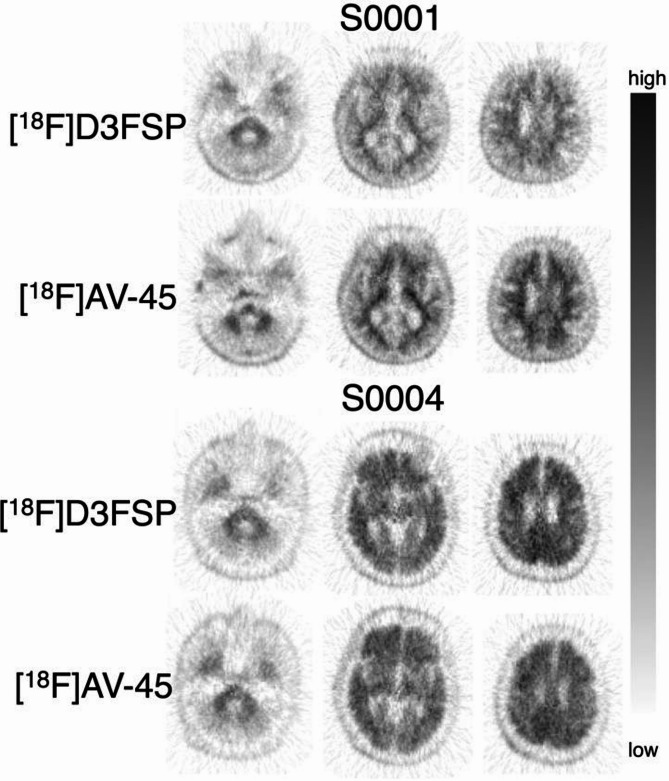

Results: Eight patients, clinically diagnosed with Alzheimer's disease, had an average age of 61.1 ± 10.0 years, and an average MMSE score of 21 ± 4. Each patient underwent paired 90-minute dynamic PET/CT scans separately within a few weeks (323 ± 31 MBq of [18F]D3FSP or [18F]AV45; florbetapir f18). SUVR (50-70 min) and Distribution Volume Ratio (DVR) of 43 brain regions were evaluated. The average SUVR across cortical gray matter was 1.65 ± 0.21 for [18F]AV45 and 1.65 ± 0.23 for [18F]D3FSP, while global DVRs were 1.36 ± 0.14 and 1.37 ± 0.13 for [18F]AV45 and [18F]D3FSP respectively. Strong correlations (R2 = 0.8-0.9) were observed between tracers for both SUVR and DVR, with slopes of ~ 0.9 (SUVR) and ~ 1 (DVR). No image artifacts or confounds influenced the visual interpretation of [18F]D3FSP compared to [18F]AV45.

Conclusions: Results showed no difference between [18F]D3FSP and [18F]AV45 and no benefit of deuteration at the N-methyl site. Even so, [18F]D3FSP may be a useful alternative for PET/CT imaging of Aβ deposits in the brain as its binding characteristics were very similar to its non-deuterated analog, the FDA-approved drug [18F]AV45.